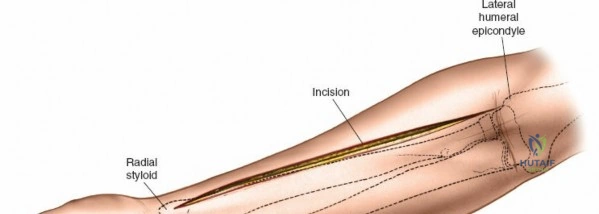

Incision: A separate straight longitudinal incision is made over the dorsal aspect of the forearm, centered approximately between the ulna and radius, extending from just distal to the lateral epicondyle to the wrist.

This image shows the dorsal longitudinal incision, made directly over the extensor compartment, providing access for decompression. -

Release of Dorsal Compartment: Identify the investing fascia over the extensor muscle group (ECU, EDM, EDC, supinator). This fascia is incised longitudinally throughout the length of the incision. Ensure full decompression of all muscle bellies.

- Proximal Consideration: The supinator tunnel, through which the posterior interosseous nerve (PIN) passes, should be carefully inspected and released if necessary, though it is less commonly a primary compression site in acute compartment syndrome.

The dorsal fascia is incised here, allowing the extensor muscles to expand. The extensor digitorum communis and other dorsal muscles are visible.

- Proximal Consideration: The supinator tunnel, through which the posterior interosseous nerve (PIN) passes, should be carefully inspected and released if necessary, though it is less commonly a primary compression site in acute compartment syndrome.